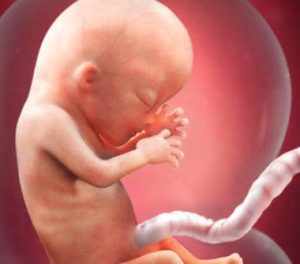

임신 13주차는 임신 중기의 시작이고 배 속의 태아도 또 다른 발달 단계에 접어 들게 된다. 임신 13주차에 태아의 크기는 6.5~10cm, 무게는 13~10g 정도이다. 이때부터 태아의 얼굴에 고유한 특징이 생기기 시작한다. 그 밖의 다른 변화에 대해 아래에서 계속 살펴보자. 매우 놀랍고 흥미진진하다!

태아의 눈과 귀가 최종적으로 자리잡는다. 그리고 대단히 놀랍게도 지문이 생긴다. 또한 가장 발달한 태아의 부위 가운데 하나가 뇌다. 장기를 덮어 보호하는 골격 구조처럼 발달한다. 이 시기에는 머리가 태아 전체 크기의 절반 가량을 차지한다.

이때부터 태아의 몸이 더욱 빠르게 성장하기 시작하고 나름의 신체 비율을 갖추게 된다. 사실, 태어날 때 아기 머리는 몸의 1/4를 차지한다.